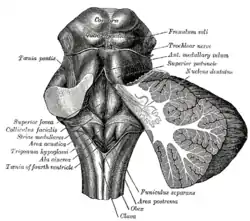

Rhomboid fossa. (Colliculus facialis labeled at center left.) | |

The facial colliculus is an elevated area located in the pontine tegmentum (dorsal pons), within the floor of the fourth ventricle (i.e. the rhomboid fossa). It is formed by fibres from the facial motor nucleus looping over the abducens nucleus. The facial colliculus is an essential landmark of the rhomboid fossa.[1]

The facial colliculus occurs within the rhomboid fossa (i.e. the floor of the fourth ventricle) where it is placed lateral to its (midline) median sulcus.[1]